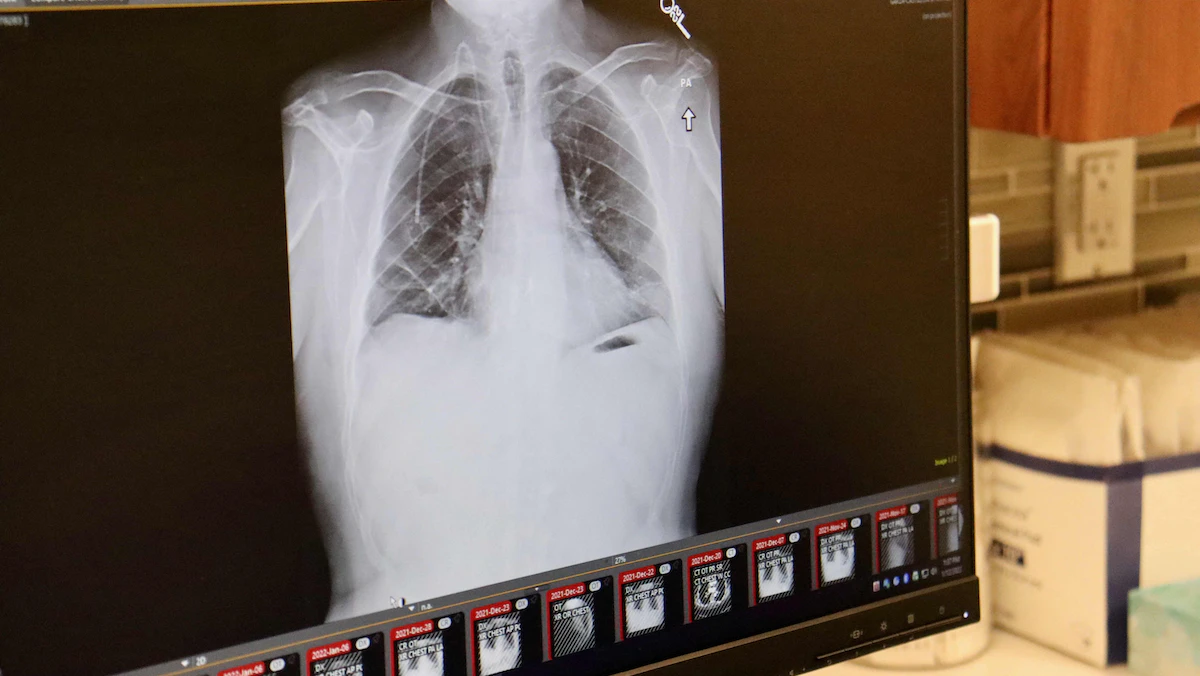

صورة أشعة لمريض تم زراعة رئتين جديدتين له بعد إصابته بسرطان الرئة واستئصال رئتيه الأصليتين في شيكاغو بالولايات المتحدة الأميركية، 12 يناير 2022 - AFP